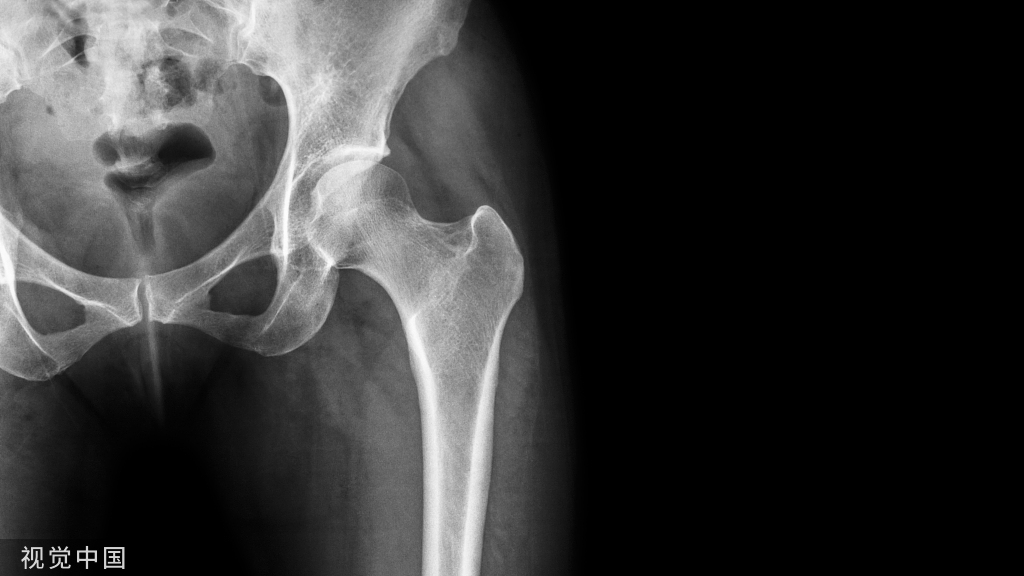

据统计,临床常见的骨质疏松症中 8%~15% 的人并非因为缺钙、维生素 D 或疾病引起,而是由药物导致体内矿物质代谢紊乱所致,临床上又称药源性骨质疏松症。今天我们一起来扒一扒那些可导致骨质疏松的药物